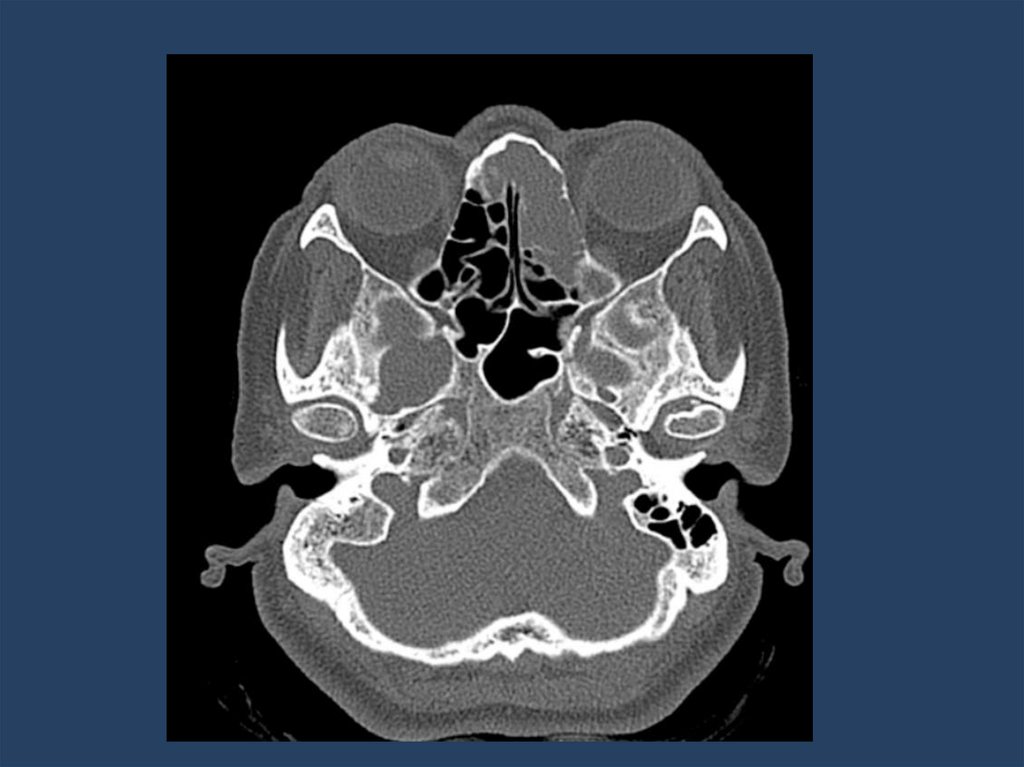

2. Лучевая диагностика:

Компьютерная томография (КТ) — метод выбора.

– Позволяет оценить костную деструкцию.

– Определяет точную локализацию и распространенность процесса.

– Характерные признаки: одностороннее затемнение пазухи, гомогенное образование

мягкотканной плотности, иногда с очагами обызвествления. Важный признак — симптом

"контралатерального отклонения" перегородки носа.